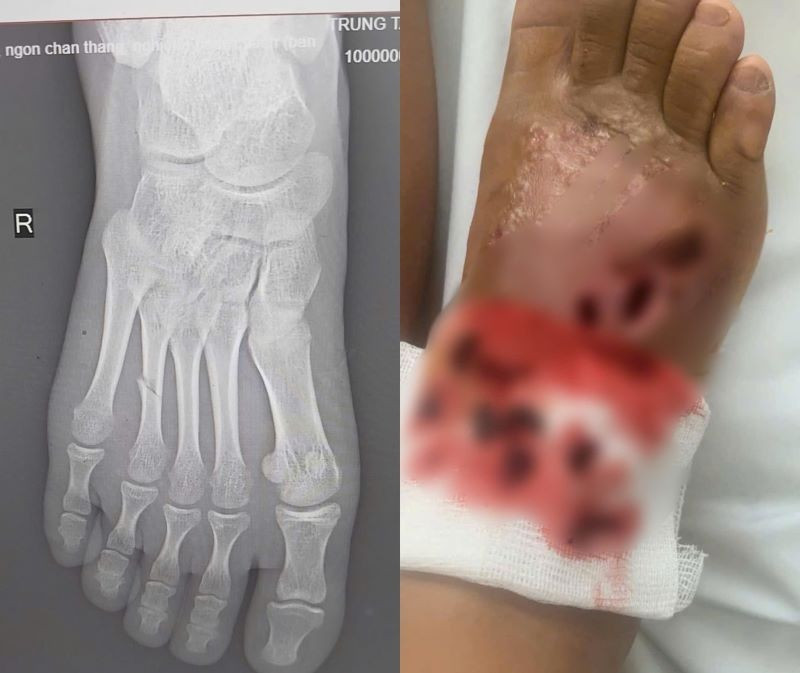

Trung tâm Y tế huyện Đoan Hùng (Phú Thọ) vừa tiếp nhận bệnh nhi N. T. T. T., 14 tuổi, ở Sơn Dương, tỉnh Tuyên Quang, trong tình trạng bàn chân phải sưng nề, đau nhức dữ dội, có nhiều ổ loét sâu đang hoại tử, dịch mủ chảy ra và có dấu hiệu nhiễm trùng lan rộng sau khi tự điều trị bằng phương pháp bó thuốc nam tại nhà.

Trước đó 14 ngày, bệnh nhi bị ngã gãy chân, thay vì đến bệnh viện để được điều trị kịp thời, gia đình bệnh nhi lại chọn phương pháp bó thuốc nam tại nhà.

Chỉ sau 5 ngày, vết thương đã bắt đầu sưng to, đau nhức dữ dội, chảy dịch mủ và có mùi hôi. Sau khi thấy triệu chứng tiến triển nặng hơn, gia đình đưa cháu tới khám tại Trung tâm Y tế huyện Đoan Hùng.

Tại đây, sau khi thăm khám lâm sàng và cận lâm sàng, kết quả trên phim chụp X-Quang cho thấy hình ảnh bị gãy xương đốt bàn chân/nhiễm trùng nặng bàn chân phải.

Các bác sĩ đã loại bỏ ổ nhiễm trùng, điều trị kháng sinh liều cao cho bệnh nhi, bó bột hở vị trí loét. Sau 1 tuần điều trị, tình trạng nhiễm trùng được cải thiện, sức khỏe bệnh nhi ổn định.